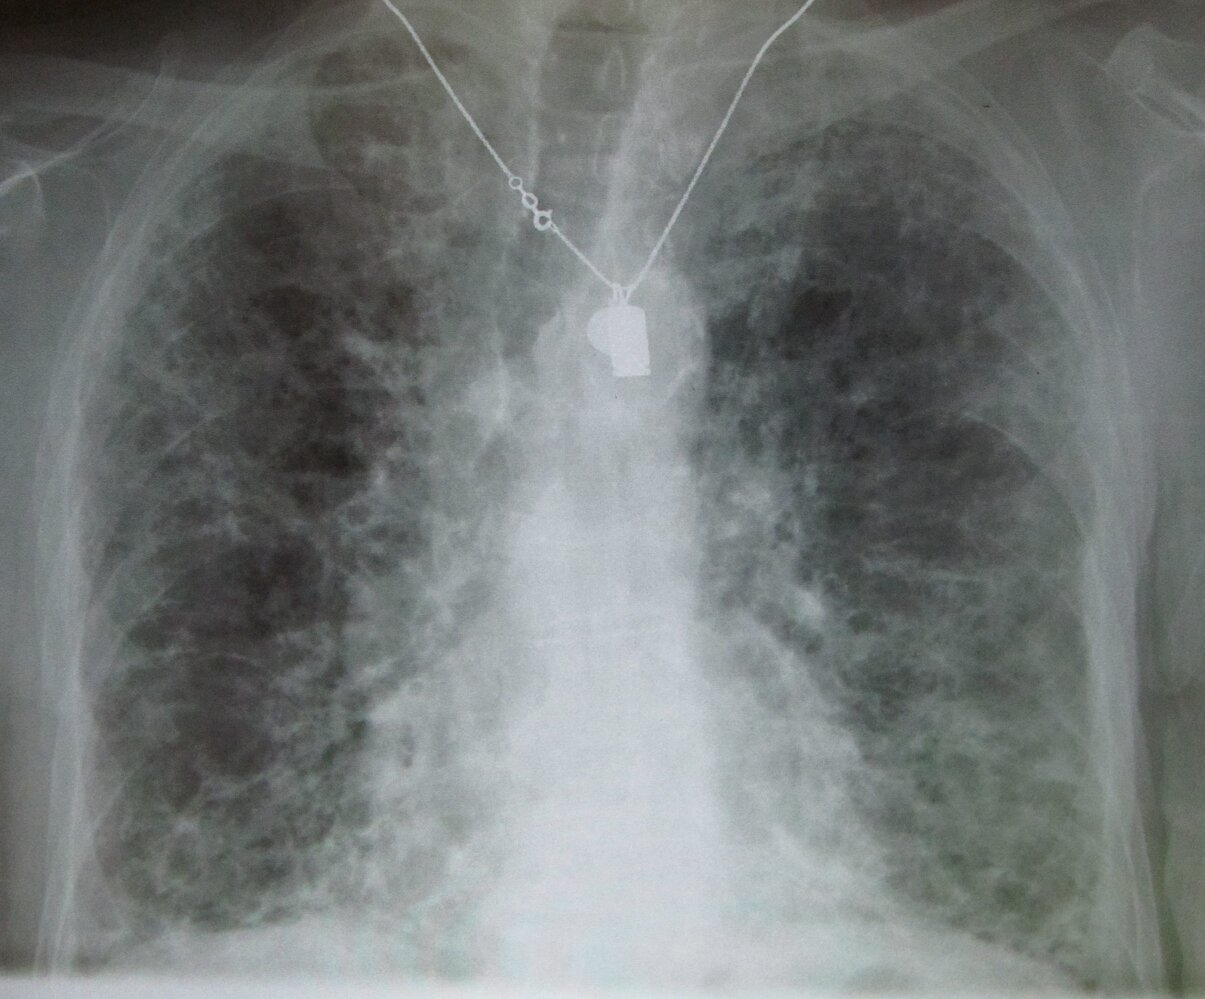

Pulmonary

• Pulmonary fibrosis

• Chronic interstitial pneumonitis

• Organizing pneumonia

• ARDS

• Solitary pulmonary mass

Pulmonary [5]

• Amiodarone-induced pulmonary toxicity (AIPT) leads to the most deaths associated with amiodarone therapy.

• Toxicity correlates more closely with cumulative dose than with serum drug levels.

• Treatment: Discontinue amiodarone and initiate corticosteroid therapy.